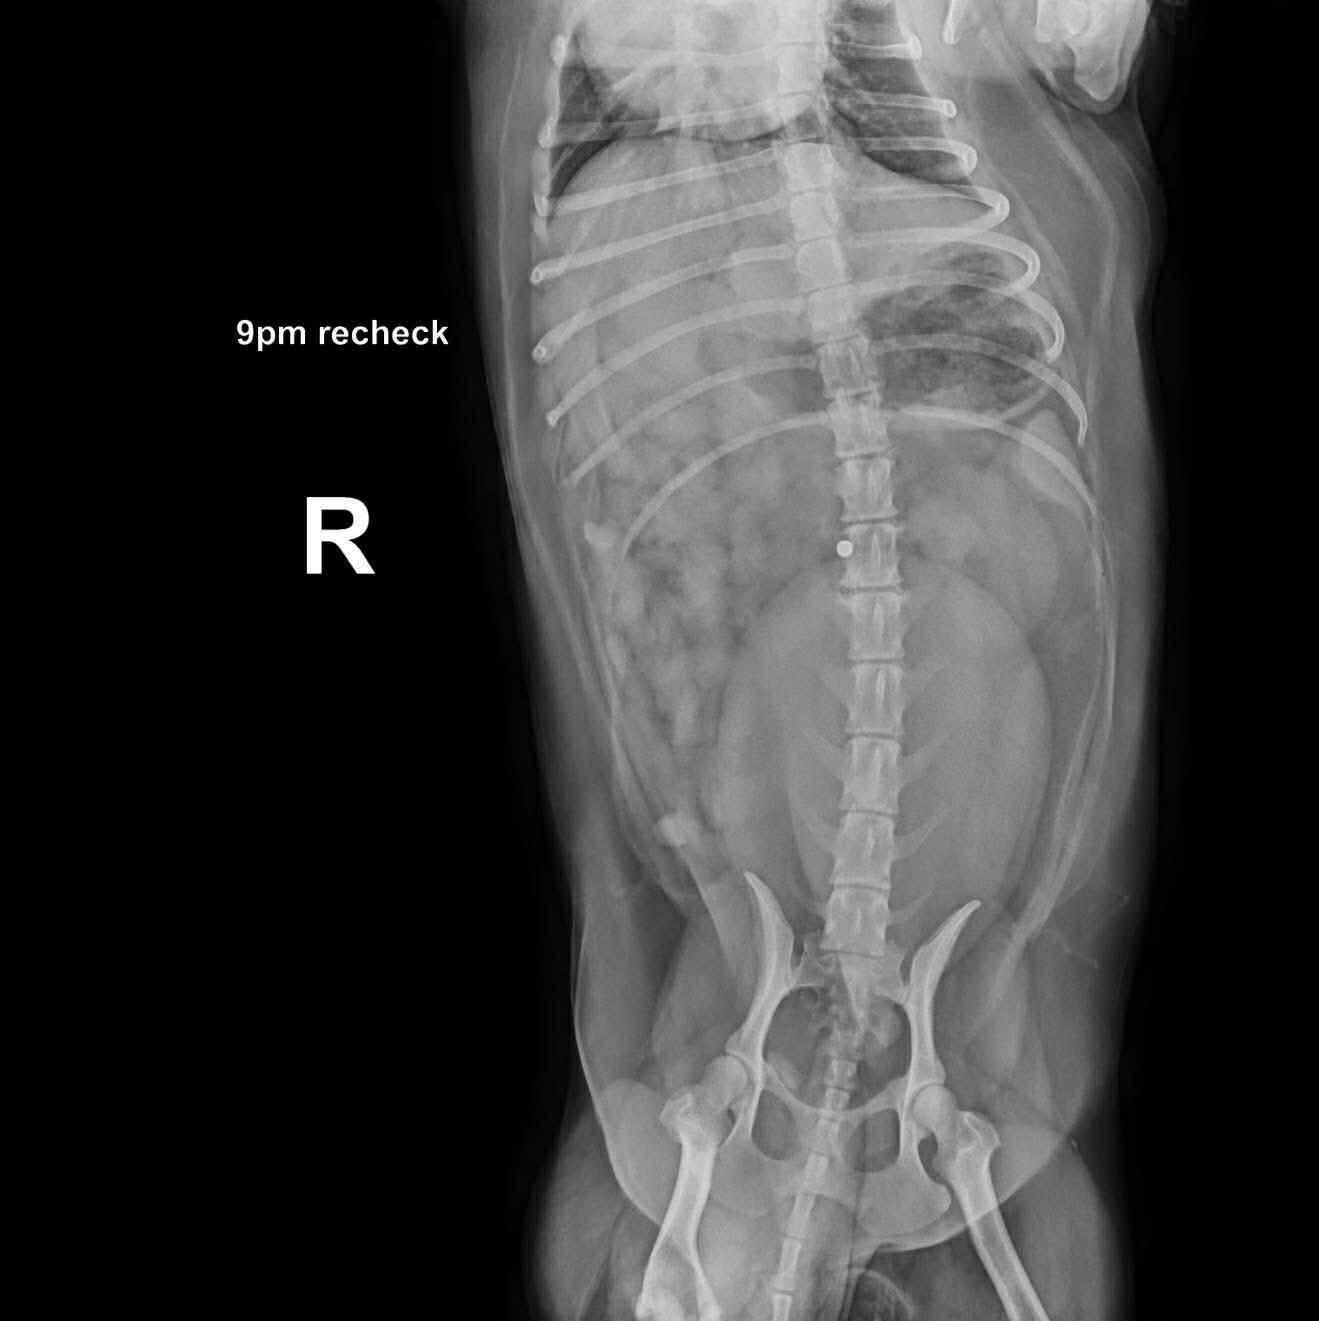

• X-rays showed no major abnormalities, but did reveal something heartbreaking—a shotgun pellet lodged in her body